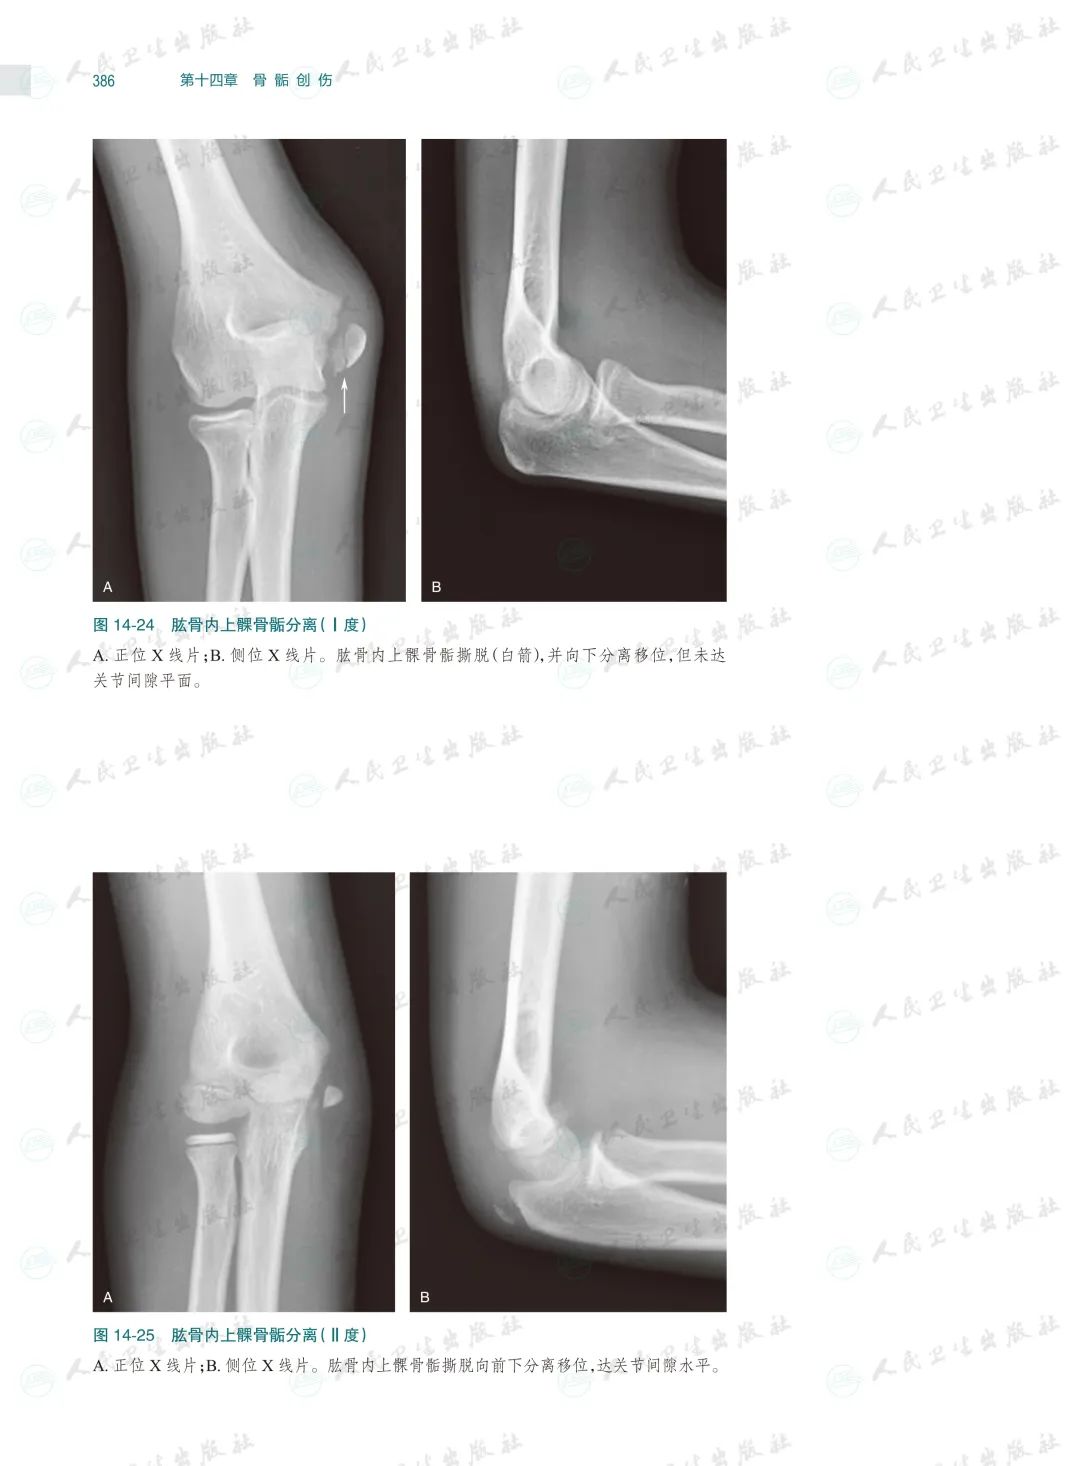

骨关节创伤是骨科临床常见病,X线检查是其最基本和最常用的检查方法。本书以临床典型病例X线检查资料为素材编写,已是第4版了,一直以来本书都因为其实用性而深受读者的喜爱,本次修订根据近几年骨关节创伤领域的#新进展,对目录进行了重新编排、对过时内容进行了修改、对清晰度和对比度欠佳的图片进行了替换,同时还充实了10多个病种的病例图片,并新增了常见骨关节创伤后遗症及并发症章节。

本书以图片展示为主,内容丰富,几乎包括了除头面部以外各个部位的骨关节创伤类型,图片清晰且有详细文字注解,每一章节的创伤类型、诊断要点和鉴别诊断均作了简要叙述。由于图片都是来自作者日常工作的资料积累,因此实用性较强,是一本不可多得的参考书。

本书在第3版基础上修订而成,是一本系统全面介绍骨关节创伤X线诊断的图谱专著。全书共十六章,前十五章每章基本按创伤类型、诊断要点和鉴别诊断体例编写,最后一章介绍常见骨关节创伤后遗症及并发症。书中共选用1270幅X线照片图,约760个病例,所选图片和病例均具有代表性,可使读者对各部位、各类型的骨关节创伤及其后遗症和并发症有进一步认识,从而提高诊断水平。本书主要供骨科医生、影像科医生及医学院校相应专业的学生使用。